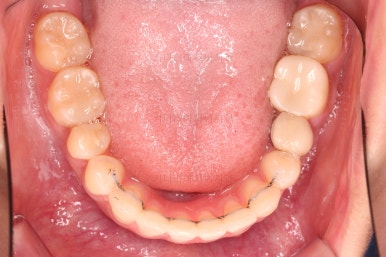

어느새 틈도 다 닫히고요.

마무리 과정만 남았습니다.

4. 마무리

틈이 다 없어졌고, 교합도 양호합니다.

무엇보다 임플란트 없이 결손부위가 깔끔하게 채워졌고요.

매우 다행으로 사랑니도 다 있었기 때문에 마치 큰 어금니가 다 있는 것과 같은 상황이 되었습니다.

역설적이게도 손상된 큰 어금니가 없었던 부위는 작은 어금니를 발치함으로 인해 오히려 치아 갯수가 모자라 보이는 상황까지 왔네요.(어금니가 결손된 부분이 더 자연스럽게 보이는 상황)

총 치료기간도 2년 반, 30개월이 걸렸습니다.

3년 이상 봐야 되는 부산사랑니교정 치료라고 말씀 드리고 시작했음에도 예상보다 훨씬 빨리 종료 되어 매우 만족스러운 치료였습니다.